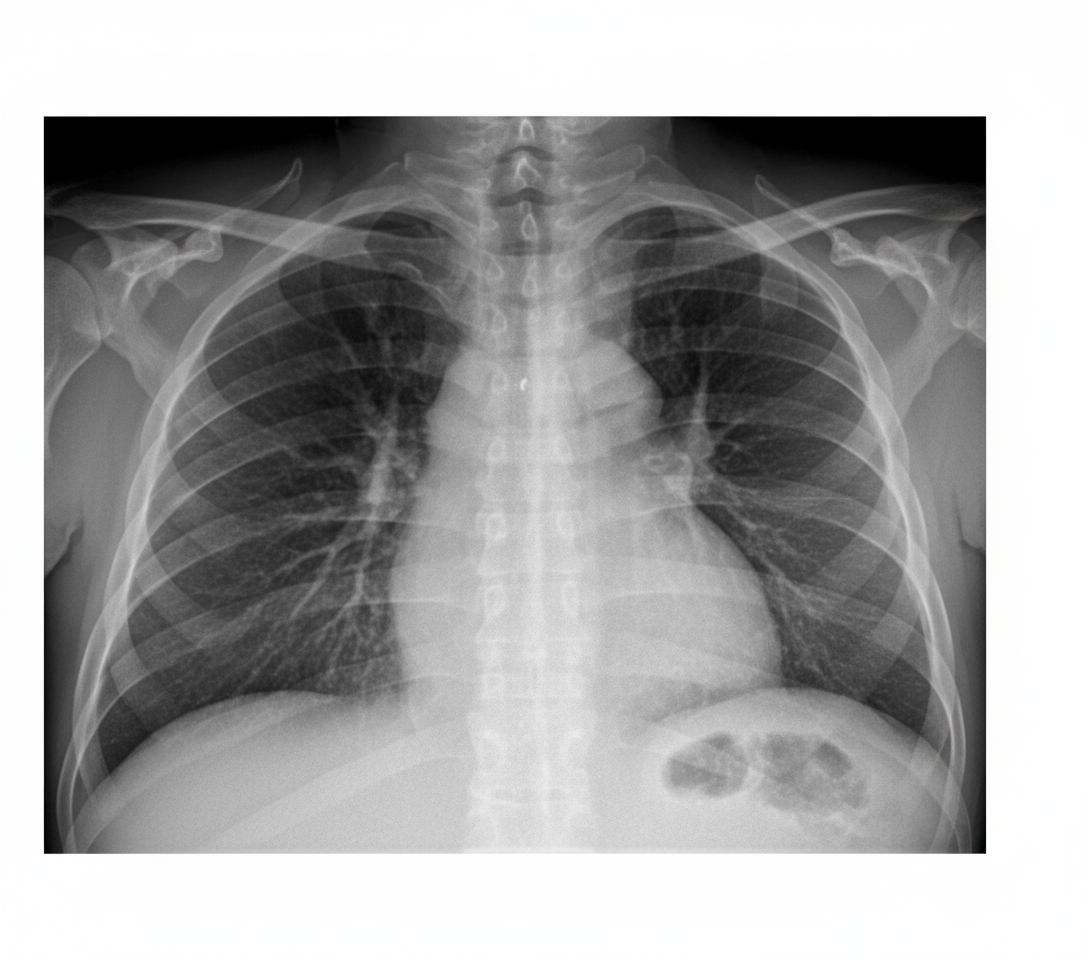

A 42-year-old female smoker with a 20-pack-year history is admitted with progressive shortness of breath. On examination, she has distant heart sounds with decreased breath sounds on lung exam bilaterally. No summation gallop is heard. ECG shows low voltage. Chest x-ray findings are shown. Which of the following findings on the chest x-ray may be associated with this presentation?

Explanation: ***Positional change of chest x-ray findings*** - In **large pericardial effusion**, the cardiac silhouette can change shape and position with patient positioning due to fluid redistributing around the heart, creating the **"swinging heart" appearance**. - This finding, combined with **distant heart sounds**, **low voltage ECG**, and bilateral decreased breath sounds in a smoker, strongly suggests a **massive pericardial effusion** compressing surrounding structures. *Pericardial rub on auscultation* - **Pericardial friction rub** is typically heard in **acute pericarditis** when inflamed pericardial layers rub against each other. - In **large pericardial effusions**, the rub is usually **absent** because the fluid separates the pericardial layers, preventing friction. *Hamman's crunch on physical exam* - **Hamman's crunch** is a crepitant sound synchronous with heartbeat, characteristic of **pneumomediastinum** (air in mediastinum). - This finding is associated with **esophageal rupture** or **pneumothorax**, not pericardial effusion, and would not explain the distant heart sounds. *Continuous diaphragm sign on chest x-ray* - The **continuous diaphragm sign** indicates **pneumomediastinum** where air outlines the diaphragm continuously across the mediastinum. - This radiological finding is seen with **air in the mediastinum**, not fluid accumulation in the pericardial space as suggested by this clinical presentation.